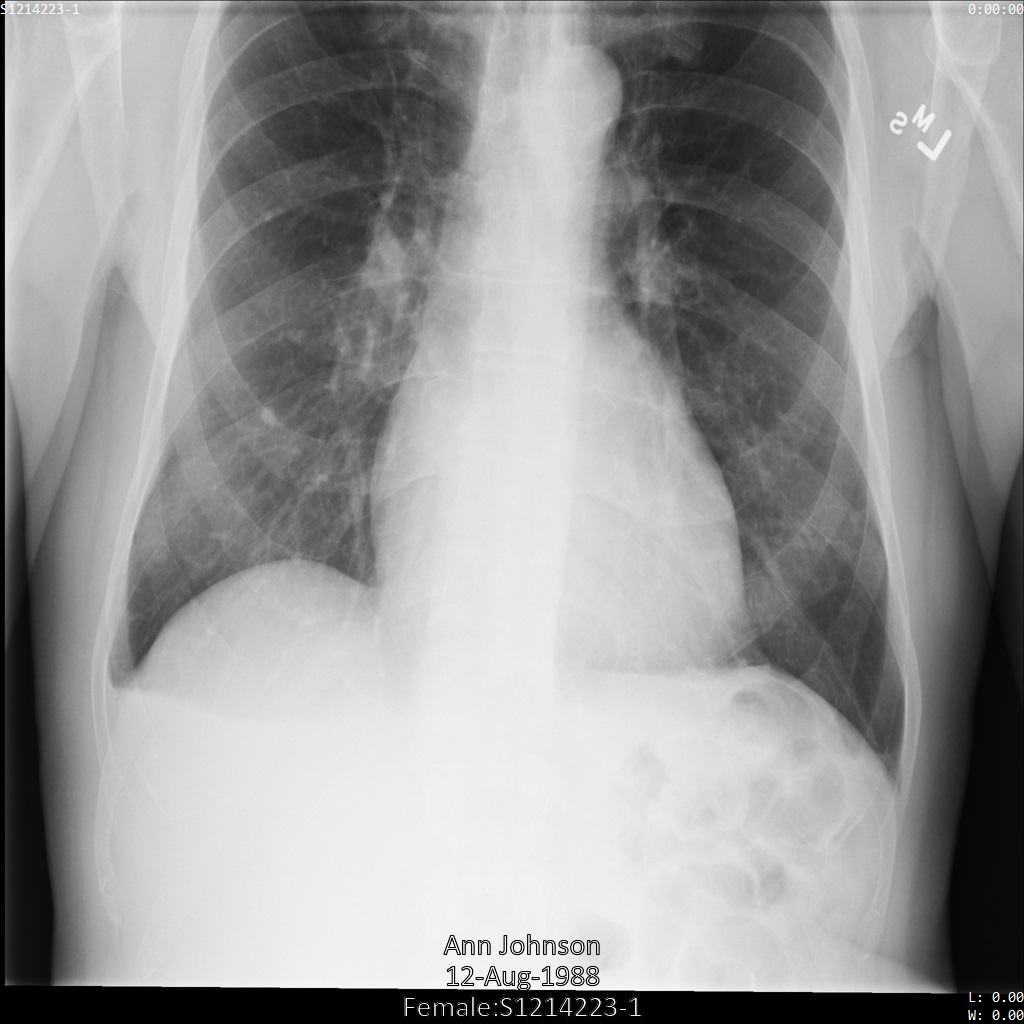

Contoh dalam panduan ini menggunakan satu instance DICOM, tetapi Anda juga dapat menghilangkan identitas beberapa instance.

Setiap bagian berikut memberikan contoh cara melakukan de-identifikasi data DICOM menggunakan berbagai metode. Output gambar yang tidak diidentifikasi disediakan dengan setiap sampel. Setiap sampel menggunakan gambar asli berikut sebagai input:

Anda dapat membandingkan gambar output dari setiap operasi penghapusan identitas dengan gambar asli ini untuk melihat efek operasi.

Setelah mengirimkan gambar ke Cloud Healthcare API, gambar akan muncul seperti berikut. Meskipun metadata yang ditampilkan di sudut atas gambar telah disamarkan, informasi kesehatan terlindungi (PHI) yang tercetak di bagian bawah gambar tetap ada. Untuk juga menghapus teks sisipan, lihat Menyamarkan teks sisipan dari gambar.